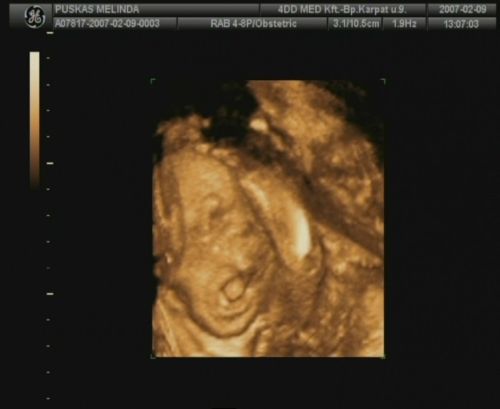

Sziasztok, megjöttem a 4D-ről. Sajnos most nincs időm a dvd-ről kimentegetni a képeket, de a telcsivel azt a hármat lefotoztam, amit kaptunk, remélem, hogy kivehető lesz azért számotokra a lényeg!

A szülésem dátuma is 2007.05.25.-re módosult, illetve a tickeremet is átjavítottam esszerint! :)

elizabeth:arik a képek, bár elég homályos, de azért ki lehet venni!!